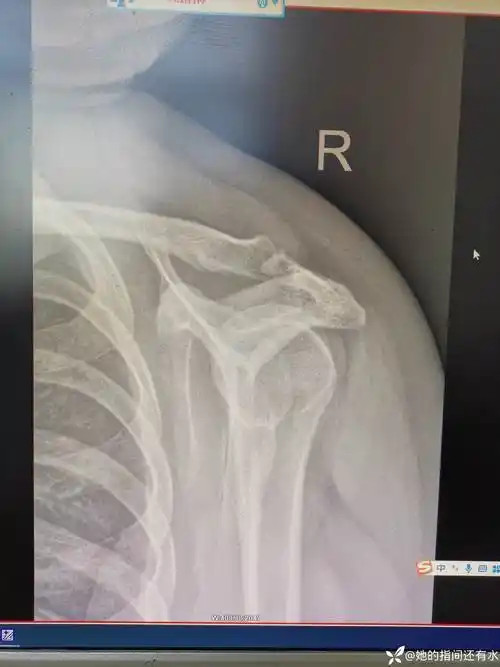

肩锁关节脱位4年

肩锁关节脱位